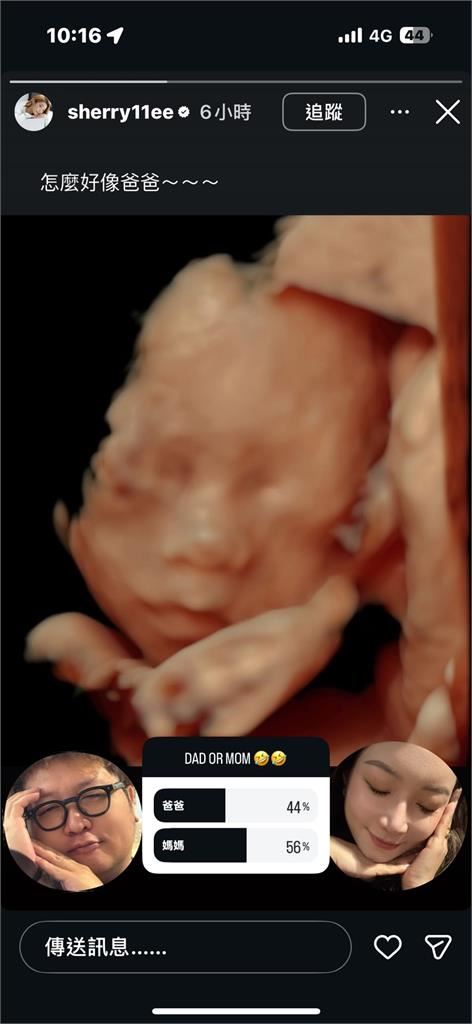

依依近來熱衷分享懷孕日常,7日就曬出產檢拍下的4D超音波照,公開女兒的外型。只見小寶寶一隻手放在臉頰、一隻手放在下巴,模樣看上去相當可愛;搞怪的依依和納豆也擺出同樣姿勢,要粉絲投票選出更像誰。雖然依依認為,女兒比較像納豆,不過從投票數來看,大部分網友覺得寶寶更像媽媽。